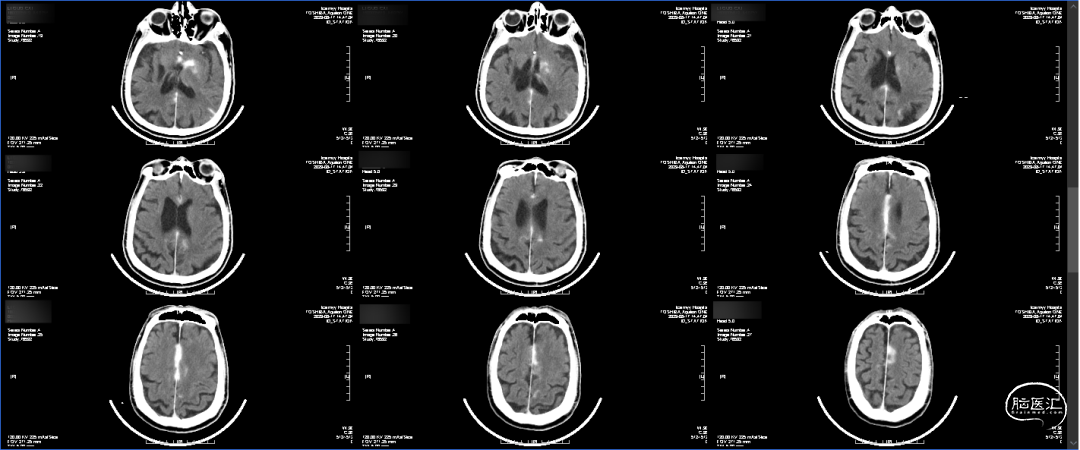

术后即刻CT:大脑纵裂高密度影,考虑出血(大脑前动脉超选困难,导丝损伤可能)。

术后第一天CT:血肿明显吸收减少。

出院前CT:出血完全吸收,左侧大脑半球未见确切梗塞灶。